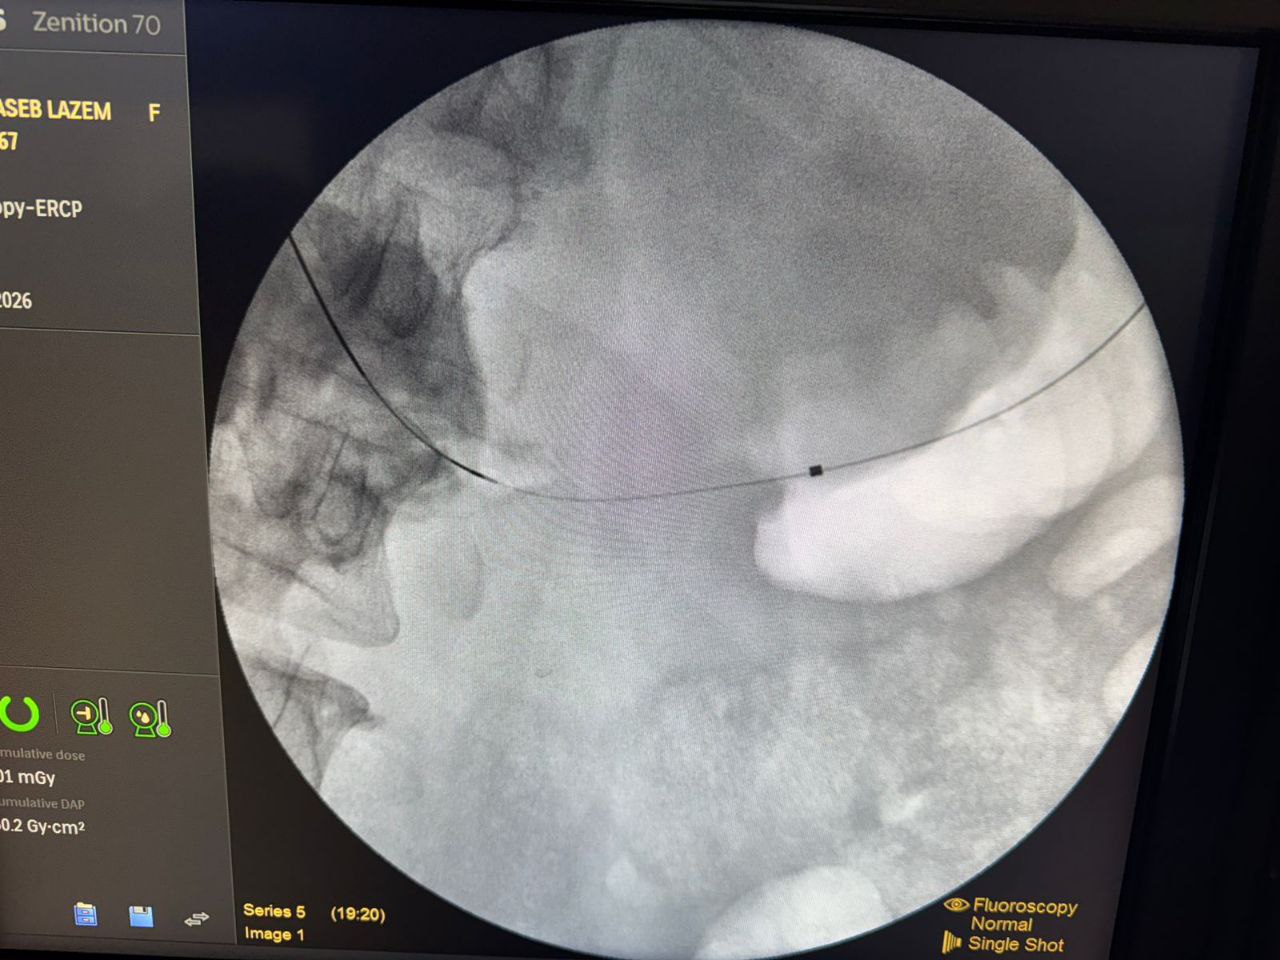

اعلنت هيئة الصحة والتعليم الطبي في العتبة الحسينية المقدسة عن نجاح اول عملية جراحية لتحويل مجرى الطعام من المعدة الى الامعاء الدقيقة في العراق.

وقال رئيس هيئة الصحة والتعليم الطبي في العتبة الحسينية المقدسة الدكتور "حيدر حمزة العابدي" في تصريخ خص به وكالة نون الخبرية ان " هذه العملية هي واحدة من العمليات التي اجراها الليلة الدكتور "خالد رجب" في مركز الجهاز الهضمي بمؤسسة وارث الدولية وهي لا تجرى الا في المراكز المتقدمة في العالم، اما في العراق فلا يتم اجراءها اطلاقا"، مشيرا الى ان " العملية هي تحويل مجرى الطعام من المعدة الى الامعاء الدقيقة

من دون عملية جراحية وانما عبر ناظور الفم فقط، وتجرى للمرضى الذي يصبح لديهم انسداد في مخرج المعدة او الاثني عشري".